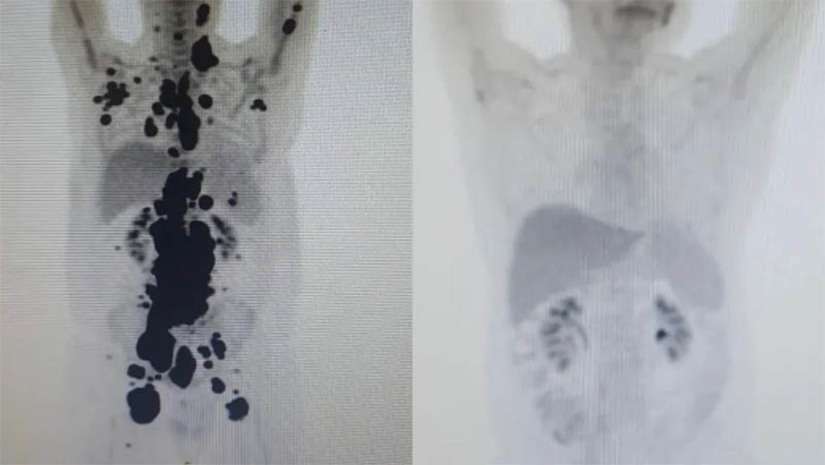

Até agora, 14 pacientes foram tratados com o CAR-T Cell com verbas da Fapesp e do CNPq, e todos tiveram remissão de ao menos 60% dos tumores. A recuperação foi no Sistema Único de Saúde (SUS).

Um deles é Paulo Peregrino, de 61 anos, que lutava contra o câncer havia 13 anos e estava prestes a receber cuidados paliativos quando foi submetido ao tratamento em abril e, em apenas um mês, teve remissão completa do seu linfoma.